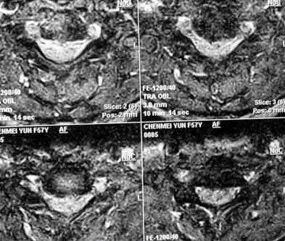

MRI成像显示颈椎椎间盘、椎体、韧带及脊髓,根据信号改变作出判断

脊髓型颈椎病MRI表现